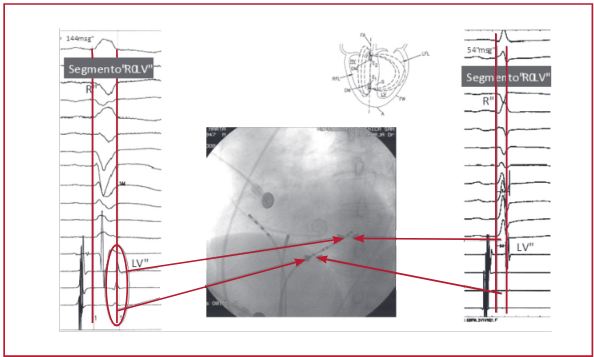

hemibloqueo anterior izquierdo, todos con miocardiopatía dilatada con fracción de eyección (FEy) < 35%; y Grupo II (n = 15), sin trastornos de la conducción con FEy conservada. A todos se les realizó un estudio electrofisiológico en el que se constataron parámet-ros en agudo de duración del QRS en mseg, distancia entre el inicio del QRS de superficie o espiga y las porciones más distales de la pared basal del ventrículo izquierdo (VI) a través del seno coronario (R-LV), el tiempo de contracción isovolumétrica (TIV) por ecocardiografía tisular, la FEy por eco-Doppler (mediciones realizadas off-line por un especialista en imágenes ecocardiográficas) y la evaluación de la dP/dtmáx del VI por catéter Millar intracavitario (solo 18 casos). Estas variables se evaluaron en estado basal (sin estimulación), con estimulación septal de alta energía (7,5 V y 1mseg de ancho de pulso), con estimulación en el ápex del ventrículo derecho y estimulación en el tracto de salida del ventrículo derecho. En la estimulación con alta energía se evaluaron umbrales de “angostamiento” del QRS.

Resultados: El tiempo del QRS, del R-LV y de contracción isovolumétrica mejoraron en el Grupo I con estimulación septal de alta energía, no así en otros sitios, incluso con mejoría de la FEy, mientras que en el Grupo II sin trastornos de la conducción la estimu-lación septal de alta energía no prolonga el QRS, el R-LV o el TIV ni mejoran la FEy, como sí lo hacen otros sitios de estimulación. La dP/dTmáx del VI presentó un incremento promedio del 14% en 16 de los 18 pacientes evaluados en agudo.